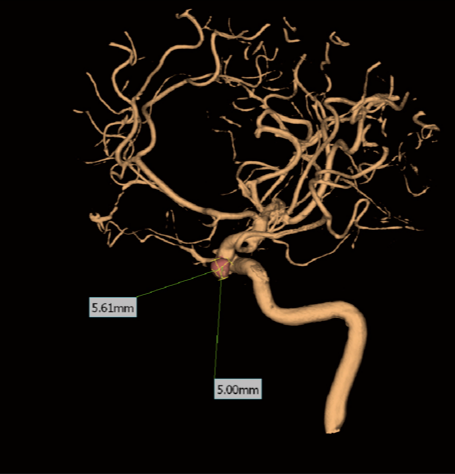

The Power of Tomography in the operating room

Combine live images with 2D and 3D projections along with tomographic slices on site

Clinical Images